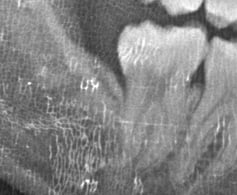

埋状歯(顎の骨または歯肉の下に埋もれて出てこない歯。)

水平埋状歯(横向きに埋もれて出てこない歯。下顎の親知らずでよく見かけます。)